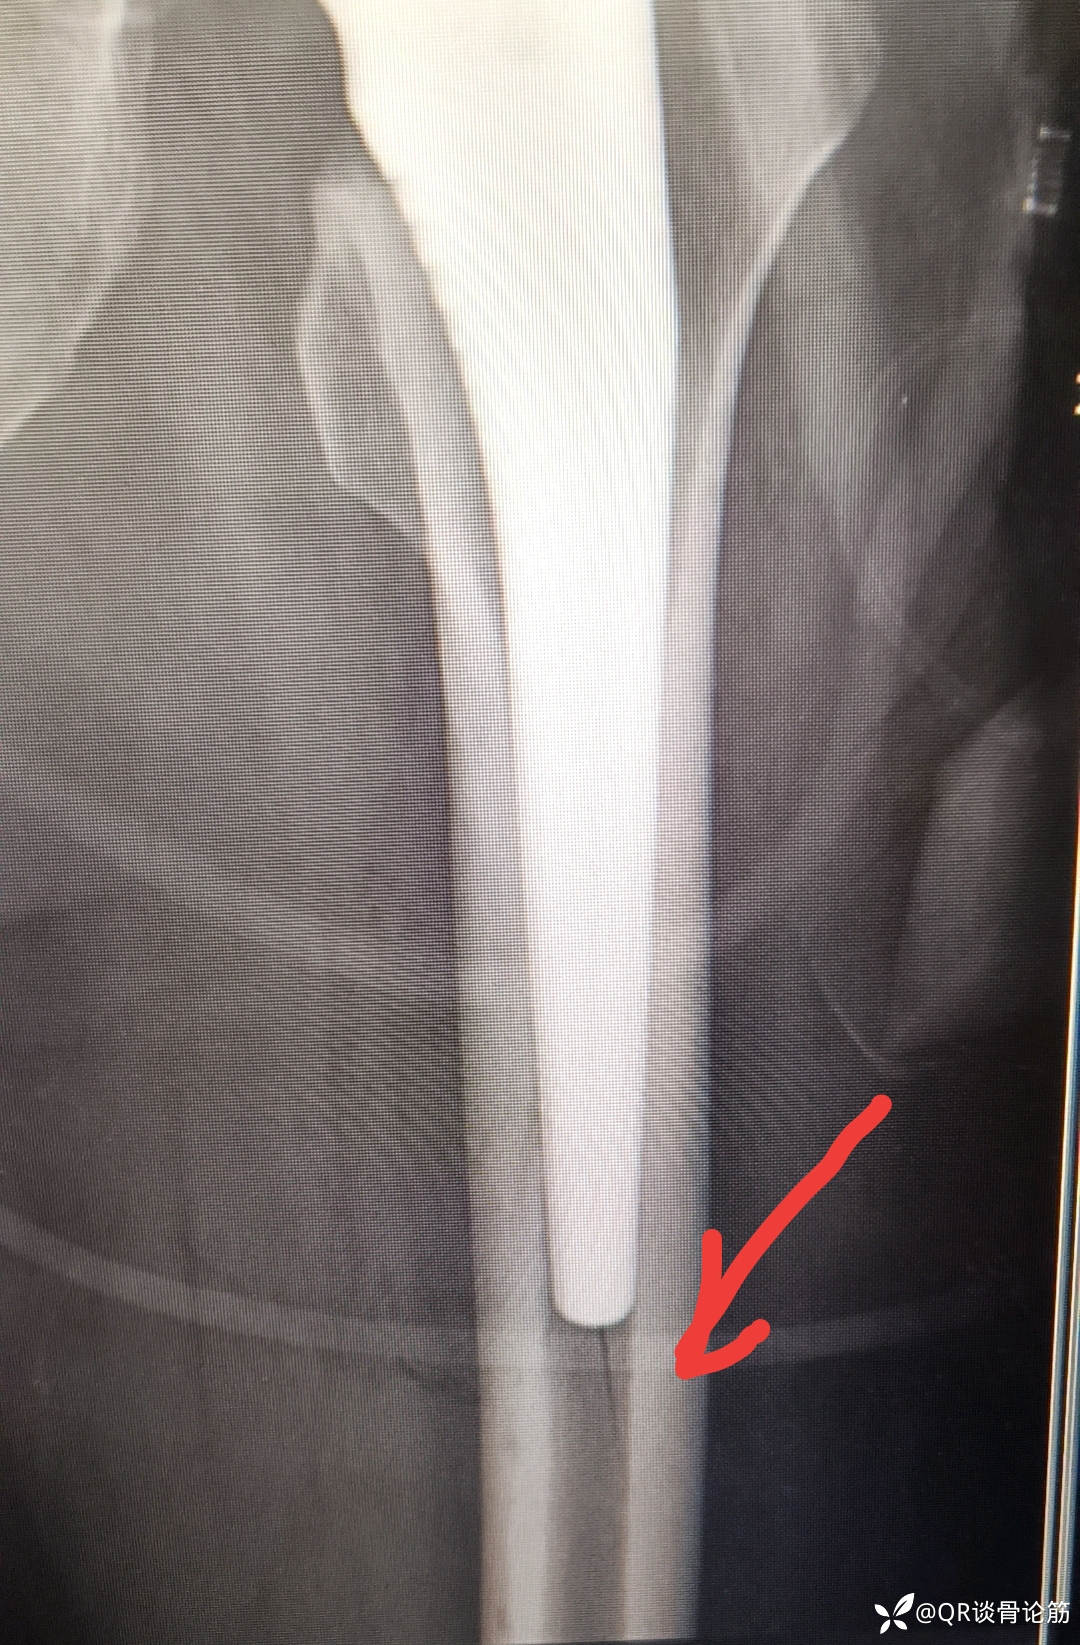

髋关节置换术中假体骨折了吗?

【治疗经过及结果】:第二天行全髋关节置换术

求有经验的老师给予指点,红色箭头标记处是否骨折了,如何处理 ,求助髋关节置换股骨侧假体术中骨折具体分型及处理。